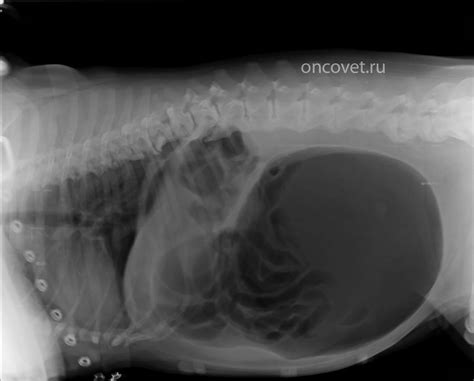

Заворот желудка у собак - симптомы, лечение, пр...

Заворот желудка у собак: причины, симптомы и ле...

Заворот желудка у собак: причины, симптомы, леч...

Заворот желудка у собак - Ветклиника «Берлога» ...

Заворот желудка у собаки

Заворот желудка у собак | БиоВет